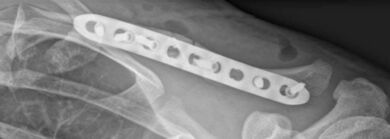

Röntgen, ggf. Computertomographie (CT) zur detaillierten präoperativen Planung. Nach ausführlicher Diagnostik erfolgt die Entscheidung über die Therapie, konservativ oder operativ. Hier entscheidet vor allem die Lokalisation des Knochenbruchs und die Dislokation, also Verschiebung der Bruchenden zueinander, sowie die Tatsache, ob die über dem Knochenbruch liegende Haut verletzt ist.

Unverschobene Brüchen ohne Hautdurchspießung können konservativ behandelt werden. Die konservative Behandlung schließt die Anlage eines speziellen Verbandes, des sogenannten Gilchrist-Verbandes, mit ein. Aus dem Verband heraus sind dabei zunächst Pendelbewegungen möglich, nach ca. vier Wochen kann die Schulter ohne Belastung normal beübt werden. Unter anderem bei instabilen, verschobenen Brüchen sowie bei Verletzung der Haut oder Schädigung benachbarter Gefäße, Nerven oder Muskeln sowie bei hohem funktionellem Anspruch, bspw. bei Sportlern ist ein operatives Vorgehen erforderlich. Hierzu werden die Bruchenden exakt zueinander ausgerichtet und zur Fixierung eine Platte auf den Knochen aufgebracht. In seltenen Fällen eines reinen Querbruchs können Titannägel zum Einsatz kommen. Auch hier ist die Anlage eines Gilchrist-Verbandes erforderlich, jedoch kann eine physiotherapeutisch unterstützte Beübung der Schulter ohne Limitation der Bewegungsausmaße ab dem ersten postoperativen Tag fortgeführt werden.

Verwendung wenig auftragender, sehr stabiler Platten- und Schraubensysteme aus Titan